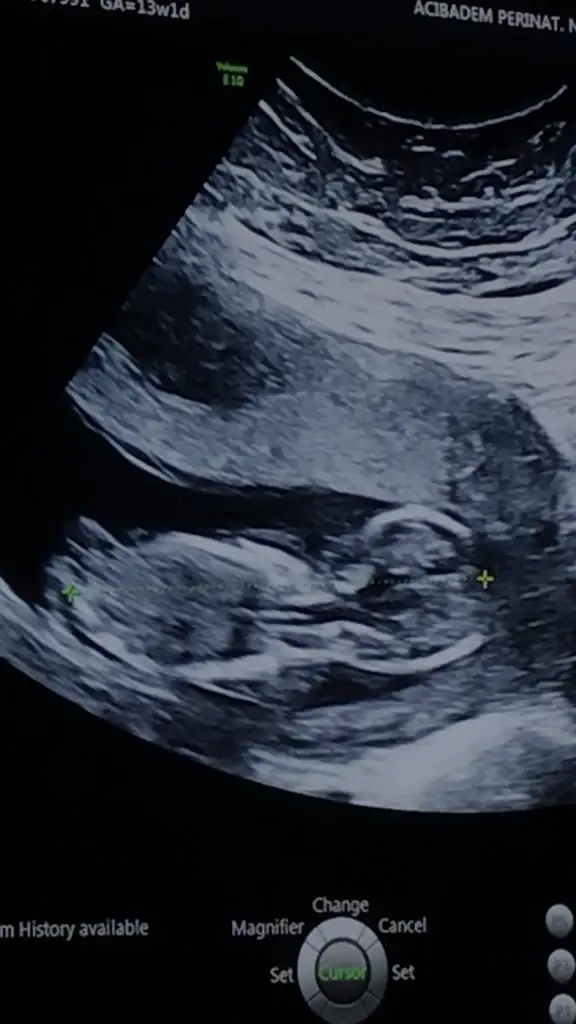

dr soylemeden siz gorun genital nub teorisi ( bebegin cinsiyeti)

Benimkinede bakar mısınız?

10+2yiz ama burda daha dr kontrolumüze var ben çıkıntı falan göremedim kızlar ya yardim edin 😅